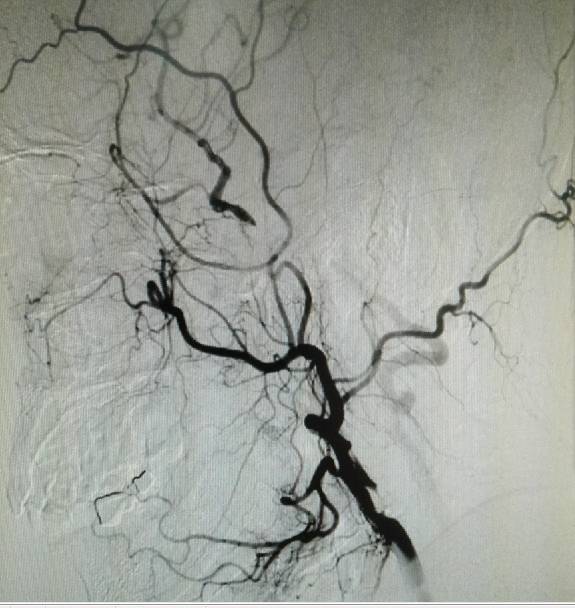

术前三个月造影:右侧颈内动脉几乎不显影。

手术过程:全麻后造影示颈内动脉闭塞,经眼动脉从颅外代偿,经前交通动脉自左侧代偿。

经动脉鞘造影,可见远端颈内动脉淡淡显影。

然后球囊扩张,植入支架。植入支架后造影示右侧颈内动脉开通。